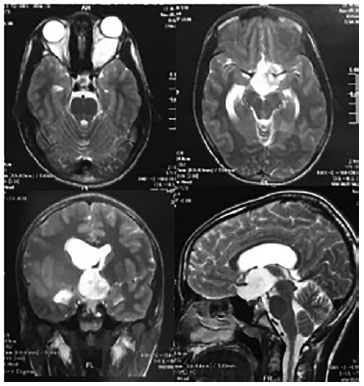

The patient is, V.G.C.S, an 11-year-old, previously healthy male who presents with a 2-year history of proptosis and progressive low visual acuity, worse in the left eye. There was no previous history of ophthalmologic disease. Ophthalmological examination showed better visual acuity of 20/25 in the right eye (RE) and light perception in the left eye (LE). Proptosis, limitation of adduction, hypertropia, and relative afferent pupillary defect were found in the LE. Biomicroscopy, tonometry, and gonioscopy findings were essentially normal in both eyes (BE). Fundoscopy of BE showed tilted optical discs with crescents of temporal atrophy and pallor in the LE disc (Figure 1). Optical coherence tomography (OCT) of the RE showed a sectoral nasal decrease in the macular layer of ganglion cells and in the layer of nerve fibers superior to the disc. OCT in the LE showed diffuse reduction in the thickness of both layers. There were no pathological systemic findings. Automated perimetry and MRI of the skull and orbits were requested. During perimetry, inferior temporal quadrantanopsia was observed in the RE and total scotoma was observed in the LE. MRI revealed an expansive and fusiform lesion (7.1 × 2.4 cm across the largest diameter) along the path of the optic nerve to the brainstem region with heterogeneous contrast uptake, suggestive of OPG, as well as asymmetrical lateral ventricles, larger on the right (Figure 2). The patient was referred to a neurosurgical service, with primary surgical management considered. Microsurgery with resection of an orbital and intracranial lesion was performed 1 month after diagnosis, without major complications. Histopathological diagnosis revealed grade 1 pilocytic astrocytoma based on the World Health Organization classification. Two months after surgery, the patient presented with a better visual acuity of 20/20 in the RE and light perception in the LE, orthotropy, without changes in ocular motility, with enophthalmos, and eyelid ptosis in the LE. Visual field testing revealed temporal hemianopsia in the RE and total scotoma in the LE.

03-fig02.jpg)